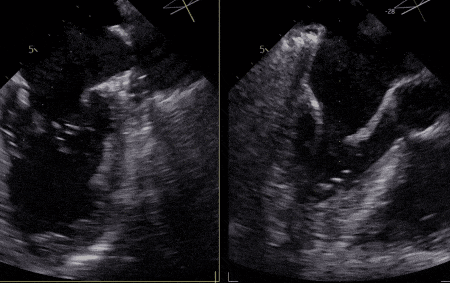

术 中

手术经股静脉置管,房间隔穿刺并置入导引导管后,送入第一枚NTR,经过左房定位到达反流位置,准确捕获并夹合前、后瓣反流严重部位,原本重度的二尖瓣反流降低为中度,决定植入第二枚NTR,最终反流降低至轻度,超声评估夹子夹合稳定、肺静脉逆流改善、平均跨瓣压差3.17mmHg,患者各项生理指标正常,手术顺利完成。

图片

▲患者术后超声影像